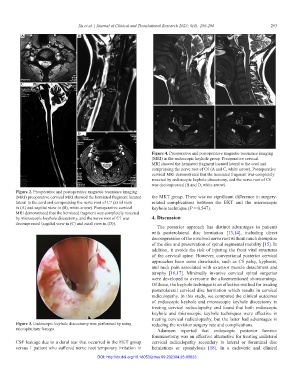

Figure 4. Preoperative and postoperative magnetic resonance imaging

(MRI) in the endoscopic keyhole group. Preoperative cervical

MRI showed the herniated fragment located lateral to the cord and

compressing the nerve root of C6 (A and C, white arrow). Postoperative

cervical MRI demonstrated that the herniated fragment was completely

resected by endoscopic keyhole discectomy, and the nerve root of C6

was decompressed (B and D, white arrow).